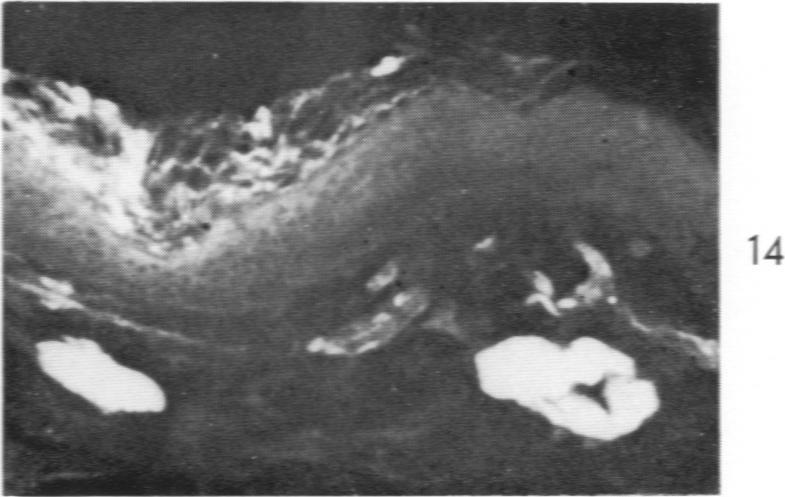

Lipoid Proteinosis (Lipoglycoproteinosis): A Histochemical Study of Two Cases.

Am J Pathol. 1962 May;40(5):599-613.